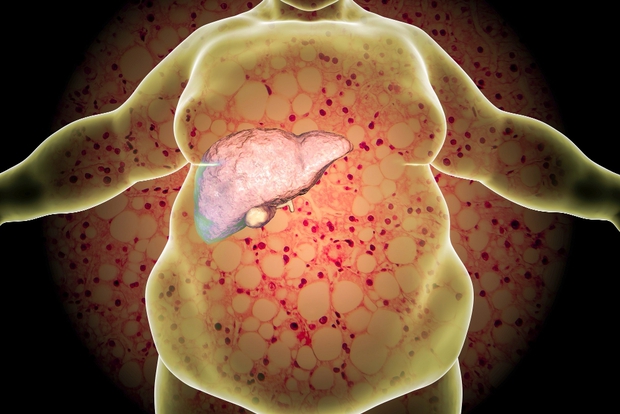

2. Cơ thể nhiều mỡ hơn những người khác: Nội tạng chứa "rác"

Mỡ, cholesterol, đạm, đường… là những chất dinh dưỡng cần thiết để nuôi sống cơ thể hàng ngày, nhưng nếu nạp quá mức sẽ trở thành một loại "rác". Việc tích tụ các chất này sẽ gây tăng mỡ thừa ở nội tạng, thậm chí khiến máu bị kết dính, làm xơ cứng thành mạch, dễ gây ra các bệnh hen suyễn, rối loạn nội tiết và các bệnh tim mạch. Từ đó, có thể gây giảm tuổi thọ.